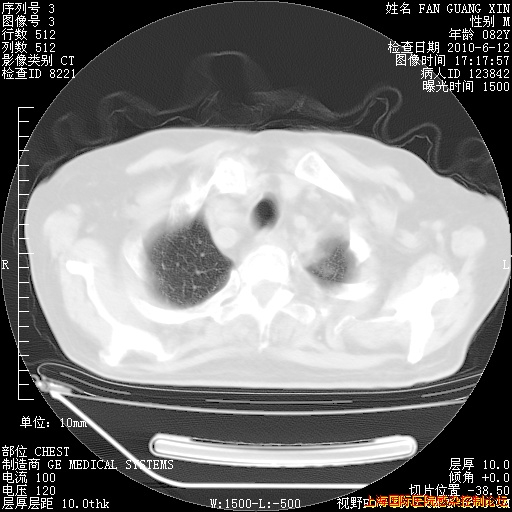

补发6月12日肺部CT肺窗

6月12日肺窗

6月12日纵膈窗